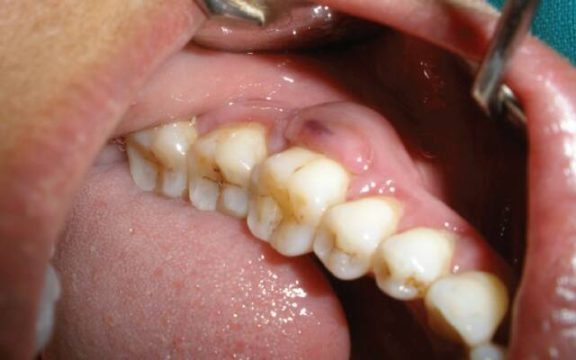

Так оно выглядит на фото:

На фото показан зубной камень